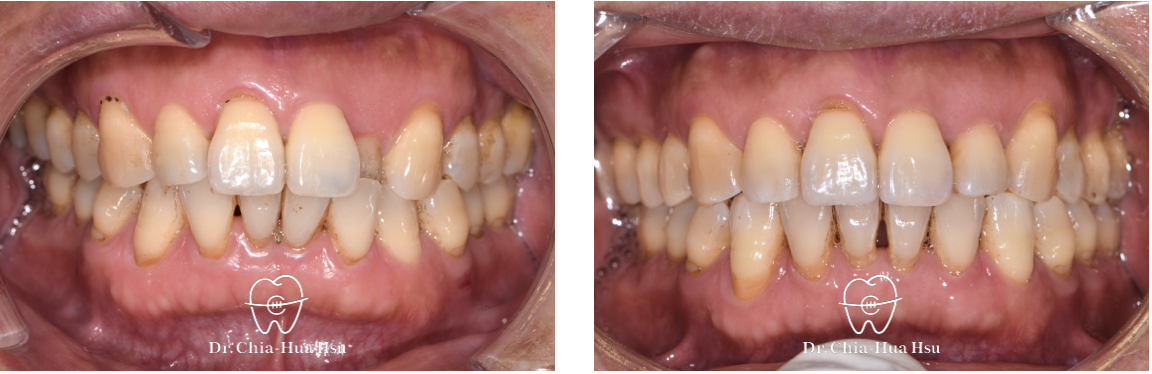

治療前

治療後